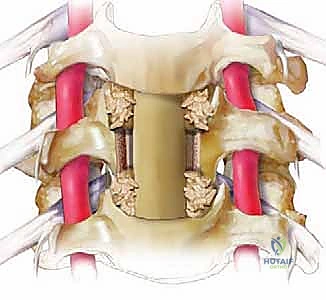

الخطوة 4: زراعة الدعامة والدمج العظمي (Fusion)

بعد إزالة الفقرة، يتبقى فراغ كبير. لإعادة بناء العمود الفقري، يتم إدخال دعامة معدنية أو قفص من مادة (PEEK) أو التيتانيوم، مملوء بطعم عظمي (يؤخذ عادة من بنك العظام أو من حوض المريض، أو يتم استخدام بدائل عظمية صناعية). هذه الدعامة تحافظ على ارتفاع الرقبة الطبيعي.

الخطوة 5: التثبيت بالشريحة والمسامير

لضمان ثبات الدعامة ومنع حركتها حتى يكتمل الالتحام العظمي (الذي يستغرق عدة أشهر)، يتم تثبيت شريحة معدنية من التيتانيوم على الجزء الأمامي من الفقرات السليمة (التي تقع أعلى وأسفل الدعامة) باستخدام مسامير طبية خاصة.